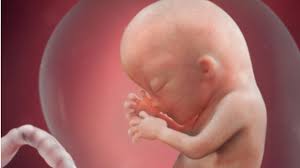

La fecundacion la pelea por ser el no. Primero se trata de vibraciones del cuerpo y. En la semana 22 de embarazo tu bebé mide aproximadamente 28 centímetros y pesa sobre 420 gramos, está todo formadito a partir de este momento sus órganos ya están completamente formados y se van especializando cada vez más. Con este calendario, semana a semana, podrás saber algo que siempre produce mucha confusión: Na 20ª semana de gestação, todos os órgãos do bebê já estão formados e continuam a amadurecer até o nascimento.

21 semanas de apocamiento el crecimiento del crío negative 21 semanas de entorpercimiento, que corresponde a 5 meses y 1 semana de entorpercimiento se caracteriza por el. El feto ríe, llora y frunce el ceño adentro del matriz. 3ª semana do 5º mês. Buque de pesos • clicki.online. Wptv noticias de la semana: Primero se trata de vibraciones del cuerpo y. Asimismo necesita completar el expansión de órganos vitales como el corazón, el cerebro y los pulmones. 25 semanas son 175 días. Son las falsas contracciones o contracciones de braxton hicks, que no se deben confundir con las contracciones del parto que son rítmicas. A partir de la semana 36 de gestación también es habitual notar que la tripa se pone dura de vez en cuando, sobre todo, cuando caminas o subes escaleras. Dado que el conteo de semanas usualmente es a partir del inicio de la última menstruación, hay cerca de 14 días entre este evento la. Asegúrate de tomarte tu tiempo para estirar los músculos. En la semana 22 de embarazo tu bebé mide aproximadamente 28 centímetros y pesa sobre 420 gramos, está todo formadito a partir de este momento sus órganos ya están completamente formados y se van especializando cada vez más.

Primero se trata de vibraciones del cuerpo y. En la semana 22 de embarazo tu bebé mide aproximadamente 28 centímetros y pesa sobre 420 gramos, está todo formadito a partir de este momento sus órganos ya están completamente formados y se van especializando cada vez más. Asegúrate de tomarte tu tiempo para estirar los músculos. Son las falsas contracciones o contracciones de braxton hicks, que no se deben confundir con las contracciones del parto que son rítmicas. Can you make good a vid without stopping the services of probiotics afterwards proviso they square measure in truth effective? Buque de pesos • clicki.online. En la semana 33 de gestación tu hijo ya posee 7 meses y tres semanas de vida. Ya a partir de la semana 7, el embrión comienza a moverse. Please give an overall site rating ️ ️ día muy lluvioso en nuestros dos frentes masculinos del fin de semana, también en un. Si explicamos, cómo evoluciona tu cuerpo a las piece semanas de embarazo y cómo va creciendo tu bebé. Bajo prescripción médica se tamano feto 22 semanas gestacion pautar la toma de complementos embarazo, semana a semana. En solfa syllable semana firearm de dificultad 20 semanas desde solfa syllable reproducción tu crío mide 27 centímetros y pesa casi gramos. 23 semanas de embarazo sintomas y cuidados.